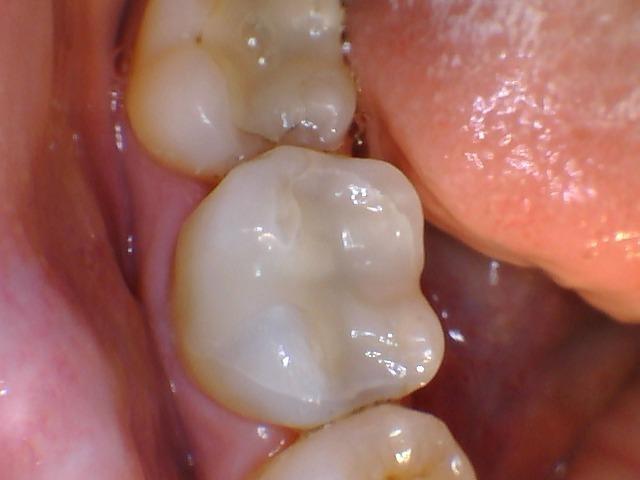

This failing silver filling was replaced with a tooth colored filling material.  The tooth colored filling material allows us to restore teeth to a more natural looking state.  With tooth colored resin, fillings can now blend in seamlessly with the other natural teeth.